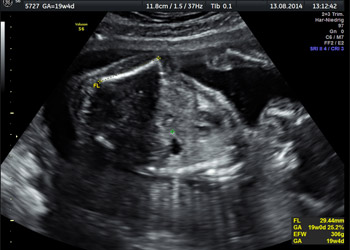

Schwangereninformationen – Zusatzleistungen >